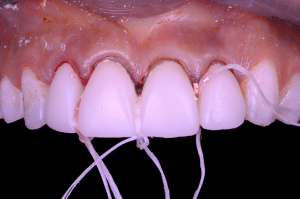

Fig 3

Les couronnes transitoires sont ainsi scellées à l’aide de Temp-Bond de Kerr, que l’on laisse complètement durcir.